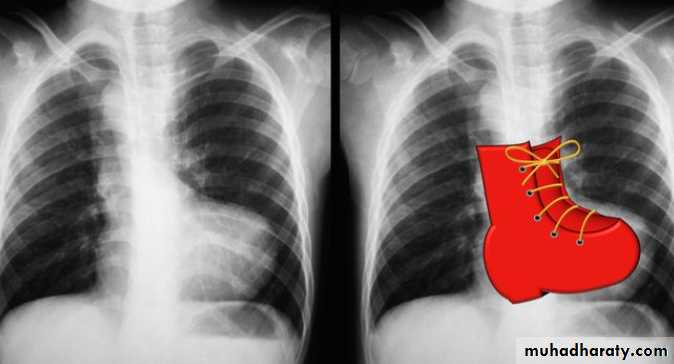

• CXR: shows boot-shaped heart (created by small main pulmonary artery and upturned apex secondary to RVH) and oligemic lung fields.